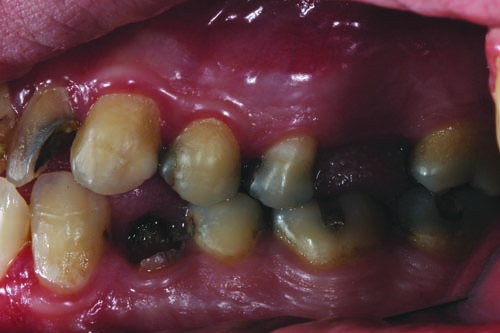

Fig. 3: The preoperative right lateral view shows evidence of the failing mesial/occlusal/distal (MOD) amalgam restorations in teeth #2, #4, #5, #29, #30, #31 and #32, as well as the need to replace missing tooth #3.